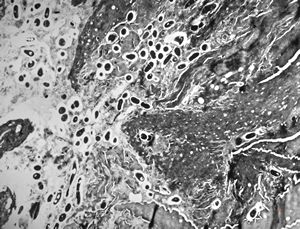

M, 57y. | dermal mycotic lesion … toluidine-blue stained semithin section